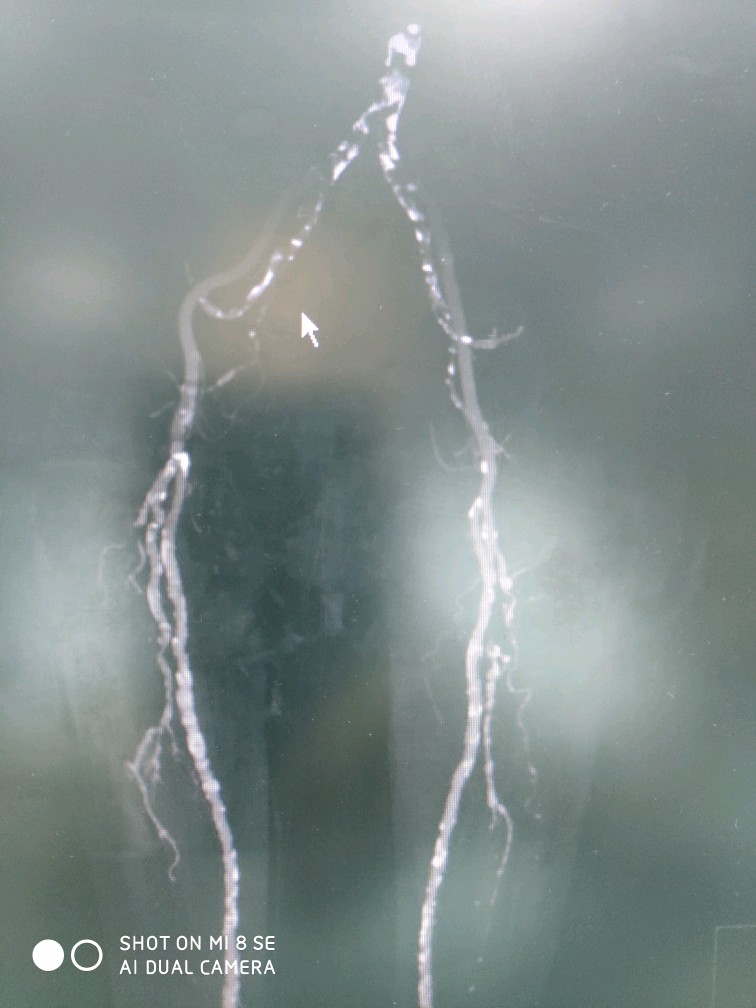

下肢动脉硬化闭塞症

下肢动脉硬化闭塞症,常发生于老年患者,与高血压,糖尿病,高血脂,吸烟等关系密切。早期临床表现肢体皮温发凉,随后导致间歇性跛行(走路疼痛伴随离距缩短,休息缓解),晚期表现为足趾颜色发黑,溃烂。

中晚期患者单纯保守治疗无效,尝尝需要外科手术干预。目前,本团队已成功开展球囊扩张,支架植入,斑块旋切等多种微创治疗术式,跻身国内一流水准!